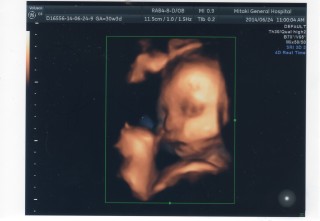

宇宙人のような顔ですがこっち向いてくれました(o^-^o) 1808gとやや大きめの男の子です☆何事もなくここまで順調に育ってくれました!もうすぐ里帰りです。少しずつ新生児グッズも揃えて準備を楽しんでいます(^^)